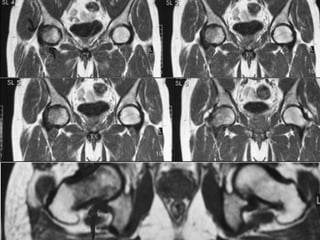

The document presents a detailed case study of a patient with transient osteoporosis of the hip (TOH) and spontaneous osteonecrosis of the knee (SONK) treated at Choithram Hospital & Research Centre in India. Over 20 years, the patient experienced multiple episodes of TOH and SONK with no history of trauma or co-morbidities, resulting in resolutions and recurrences of conditions. The information is intended for orthopedic surgery students and highlights personal experiences and case collections, with a disclaimer regarding content usage and potential controversies.